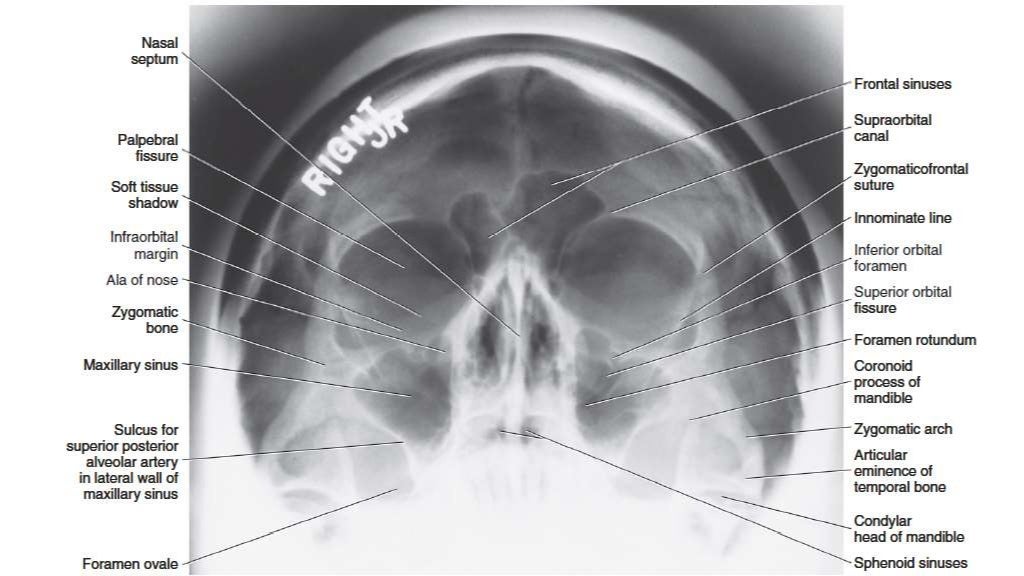

Waters View X Ray Anatomy . Lateral view, caldwell’s view, waters’ view, and submentovertex or base view. This page contains radiographic anatomy of the adult facial bones. The standard radiographic sinus series consists of four views: Occipitofrontal view (caldwell view) occipitomental (om) or waters view.

Lateral view, caldwell’s view, waters’ view, and submentovertex or base view. Occipitofrontal view (caldwell view) occipitomental (om) or waters view. This page contains radiographic anatomy of the adult facial bones. The standard radiographic sinus series consists of four views:

Waters View X Ray Anatomy This page contains radiographic anatomy of the adult facial bones. The standard radiographic sinus series consists of four views: This page contains radiographic anatomy of the adult facial bones. Occipitofrontal view (caldwell view) occipitomental (om) or waters view. Lateral view, caldwell’s view, waters’ view, and submentovertex or base view.

Normal Anatomy Radiology Key Waters View X Ray Anatomy Occipitofrontal view (caldwell view) occipitomental (om) or waters view. Lateral view, caldwell’s view, waters’ view, and submentovertex or base view. This page contains radiographic anatomy of the adult facial bones. The standard radiographic sinus series consists of four views: Waters View X Ray Anatomy.